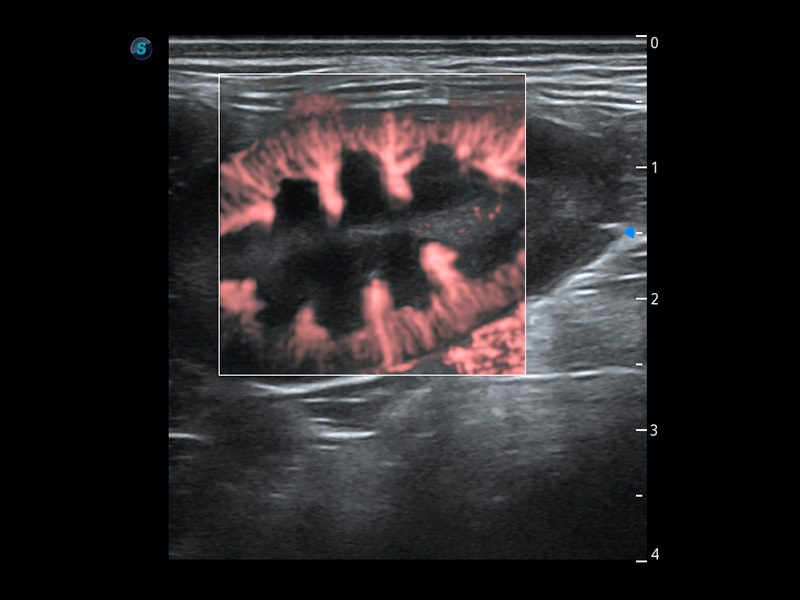

ProPet 60 作為一款高端臺式動物超聲設(shè)備,為動物醫(yī)生的日常診斷提供了一系列貼合動物臨床需求、解決臨床實際問題的高級成像功能。憑借全系列高清探頭,滿足醫(yī)生對腹部、心臟、生殖、淺表、肌骨等成像的所有需求,切實幫助您提升檢查效率,提高診斷信心。

動物是人類最親密的朋友和最值得信賴的伙伴。開立醫(yī)療也一直致力于探索動物專用的超聲影像解決方案。 全新推出的ProPet系列,是開立在動物超聲影像智能化、專業(yè)化、精準(zhǔn)化的一次跨越式革新。動物不能用言語來表述自己的不適,通過超聲影像,ProPet系列搭建了動物醫(yī)生與不同物種溝通的“橋梁”,為動物醫(yī)生注入了“治愈之力”。